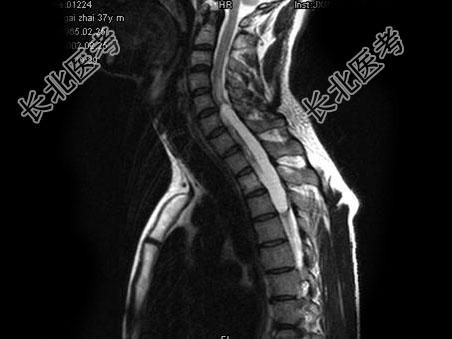

单项选择题男,37岁, 肢体活动不利、酸胀1年余,MRI扫描见椎管内长条形T1和T2高信号, 脂肪抑制序列呈低信号,应考虑为 ( )